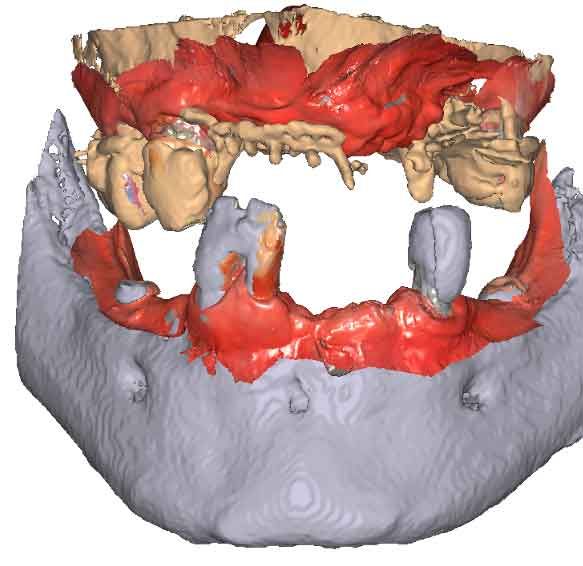

3D models - Bite scan from intra-oral scanner

Step 2 – CBCT acquisition

When traditional IOS scans lack necessary references, Cone Beam Computed Tomography (CBCT) data serves as a possible alternative. By utilizing CBCT scans, clinicians can establish accurate reference positions for treatment planning.

To be able to use CBCT data as initial models, we need to transform the DICOM file into an STL file.